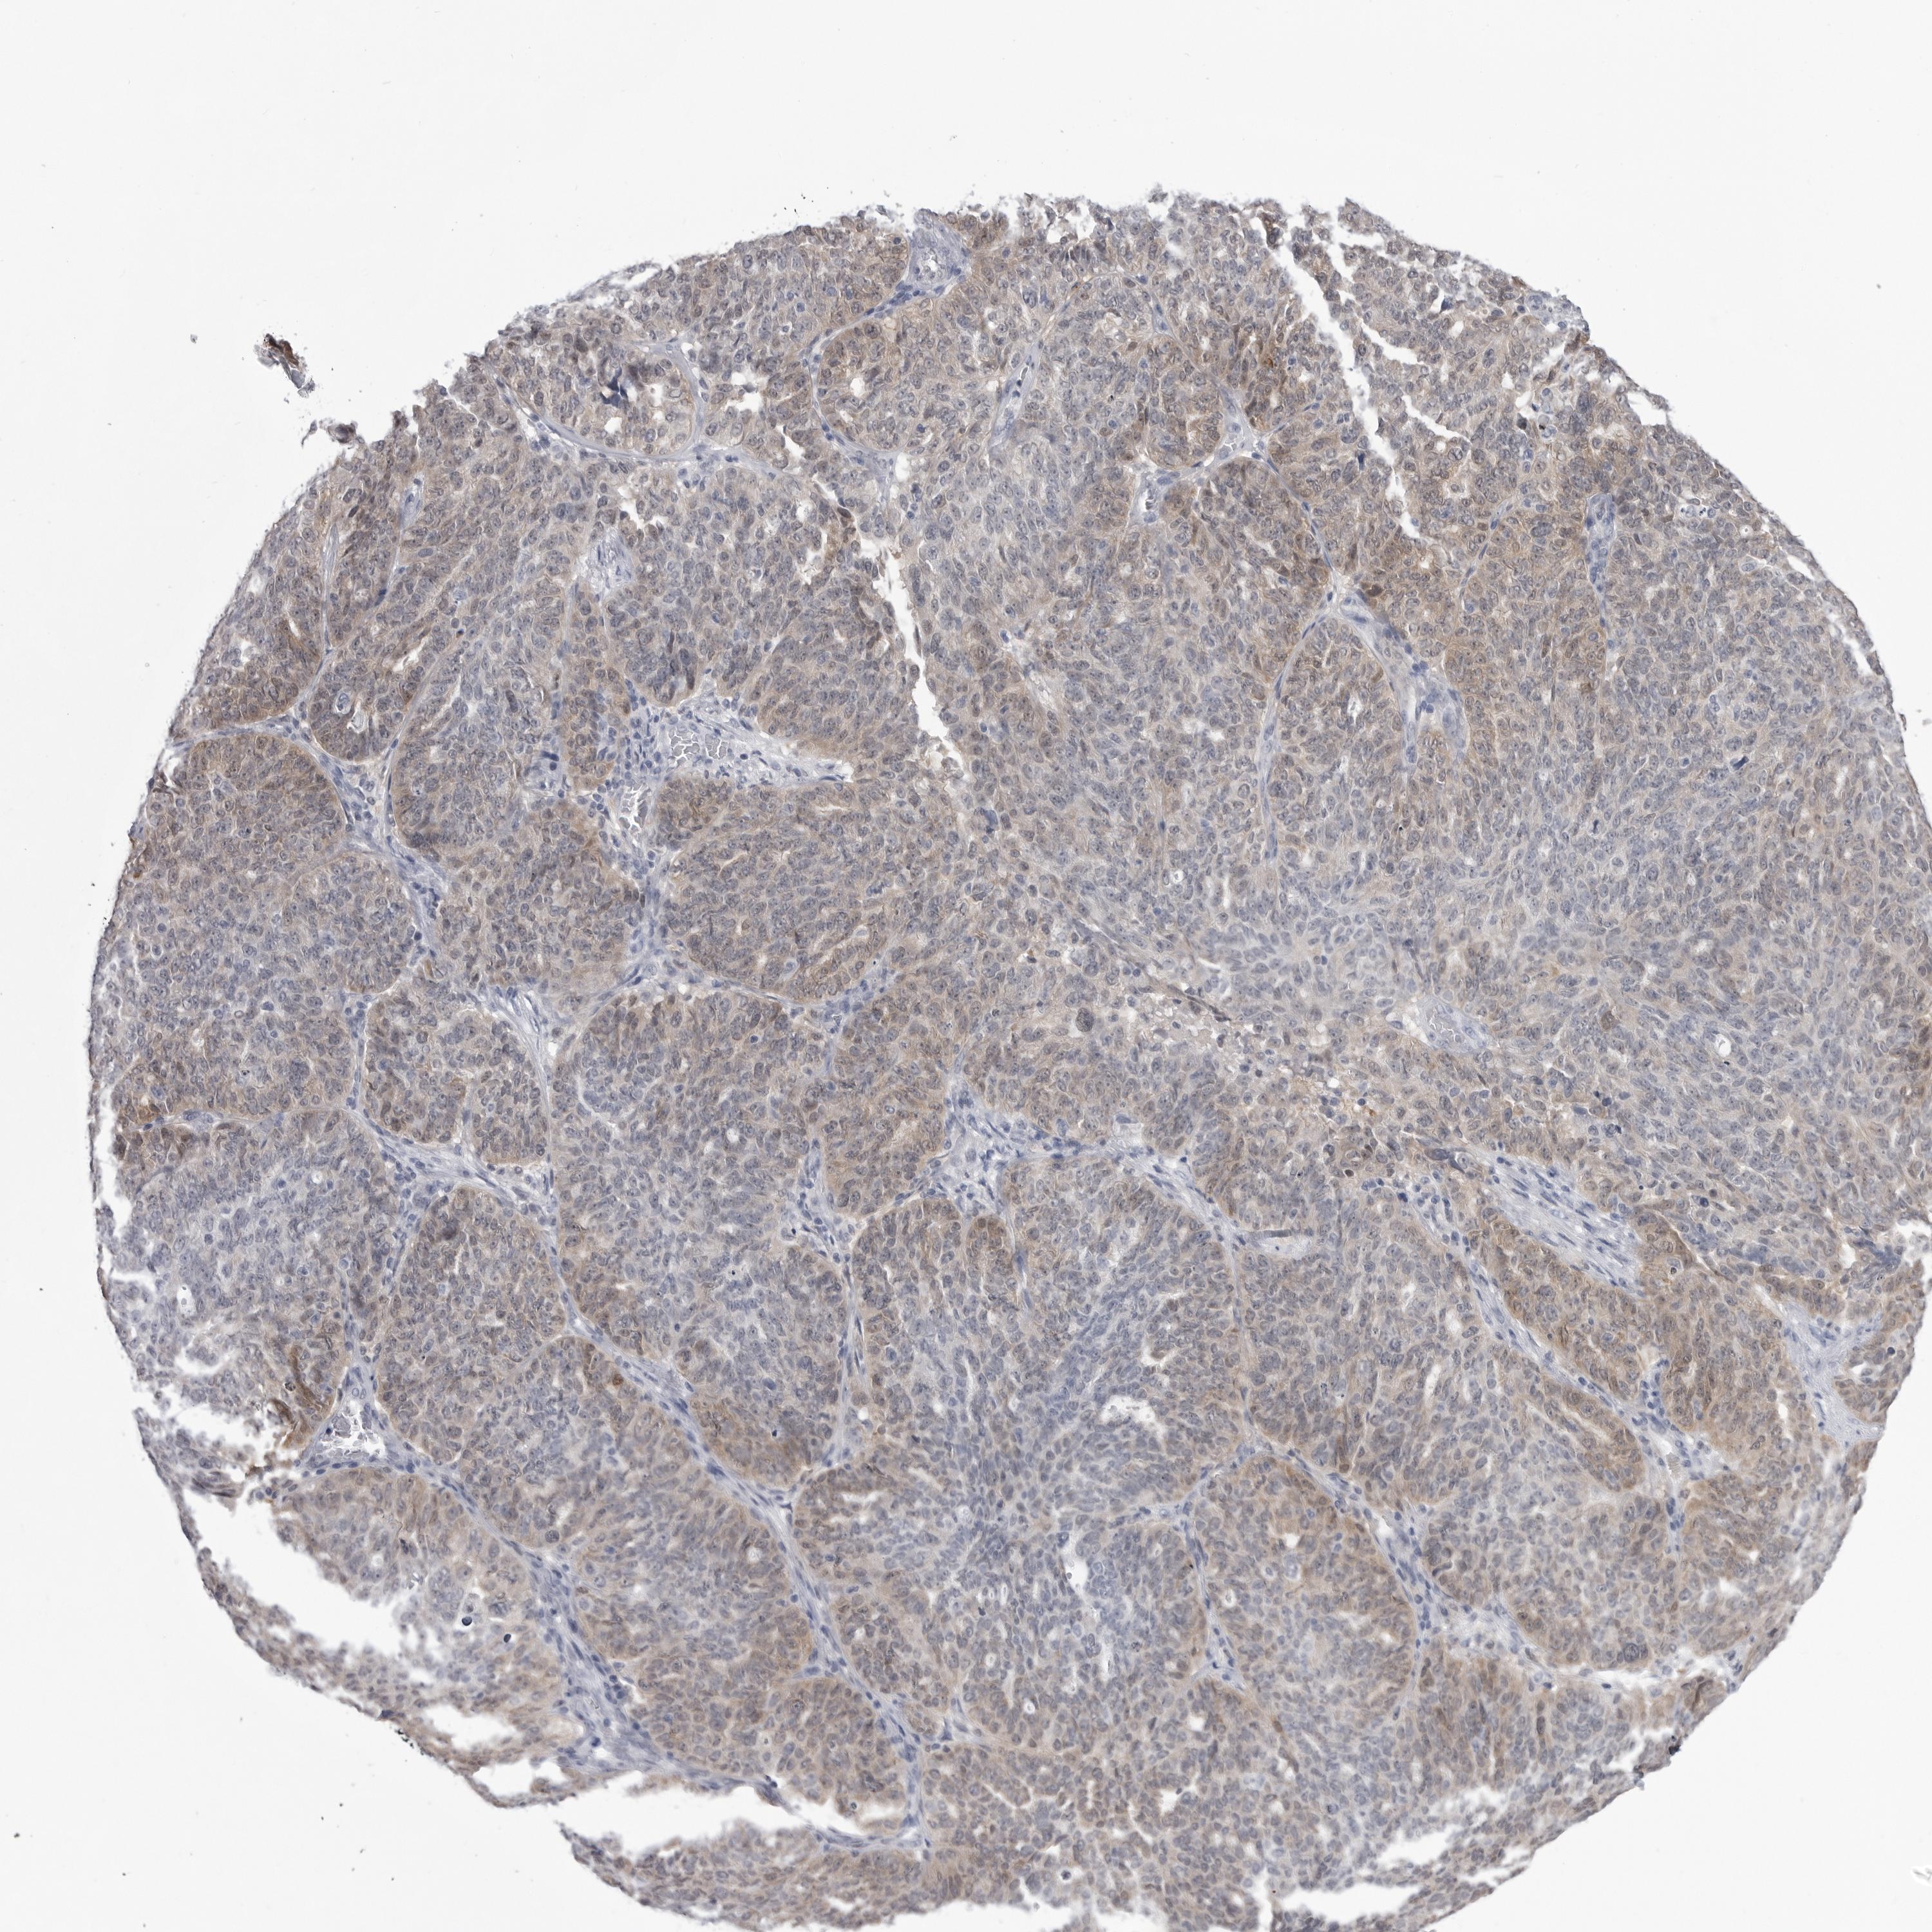

OVARIAN CANCER - Protein expressioni

A mouse-over function shows sample information and annotation data. Click on an image to view it in a full screen mode. Samples can be filtered based on level of antibody staining by selecting one or several of the following categories: high, medium, low and not detected. The assay and annotation is described here.

Note that samples used for immunohistochemistry by the Human Protein Atlas do not correspond to samples in the TCGA dataset.

Antibody stainingi

Antibody staining in the annotated cell types in the current human tissue is reported as not detected, low, medium, or high, based on conventional immunohistochemistry profiling in selected tissues. This score is based on the combination of the staining intensity and fraction of stained cells.

Each image is clickable and will lead to virtual microscopy that enables deeper exploration of all samples and also displays staining intensity scores, fraction scores and subcellular localization as well as patient and tissue information for each sample.

Antibody HPA023204

Antibody HPA027776

Staining

High

Medium

Low

Not detected

Intensity

Strong

Moderate

Weak

Negative

Quantity

>75%

75%-25%

<25%

None

Location

Nuclear

Cytoplasmic/membranous

Cytoplasmic/membranous,nuclear

Cystadenocarcinoma, serous, NOS

Carcinoma, endometroid

Cystadenocarcinoma, mucinous, NOS

Carcinoma, NOS